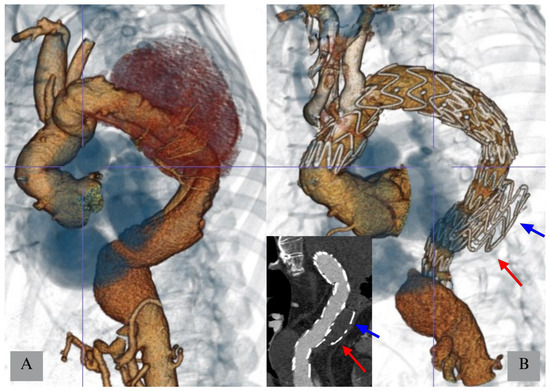

3.1.2. Temporary Aneurysm Sac Perfusion (TASP)

- Kasprzak, P.M.; Gallis, K.; Cucuruz, B.; Pfister, K.; Janotta, M.; Kopp, R. Editor’s choice—Temporary aneurysm sac perfusion as an adjunct for prevention of spinal cord ischemia after branched endovascular repair of thoracoabdominal aneurysms. Eur. J. Vasc. Endovasc. Surg. 2014, 48, 258–265. [Google Scholar] [CrossRef]

- Youssef, M.; Salem, O.; Dünschede, F.; Vahl, C.F.; Dorweiler, B. Adjunct Perfusion Branch for Reduction of Spinal Cord Ischemia in the Endovascular Repair of Thoracoabdominal Aortic Aneurysms. Thorac. Cardiovasc. Surg. 2018, 66, 233–239. [Google Scholar] [CrossRef]

- Jayia, P.; Constantinou, J.; Hamilton, H.; Ivancev, K. Temporary Perfusion Branches to Decrease Spinal Cord Ischemia in the Endovascular Treatment of Thoraco-Abdominal Aortic Aneurysms. AORTA 2015, 03, 56–60. [Google Scholar] [CrossRef]

- Harrison, S.C.; Agu, O.; Harris, P.L.; Ivancev, K. Elective sac perfusion to reduce the risk of neurologic events following endovascular repair of thoracoabdominal aneurysms. J. Vasc. Surg. 2012, 55, 1202–1205. [Google Scholar] [CrossRef] [PubMed]

- Mangialardi, N.; Lachat, M.; Esposito, A.; Puippe, G.; Orrico, M.; Alberti, V.; Fazzini, S.; Ronchey, S. The “Open Branch” Technique. Catheter. Cardiovasc. Interv. 2016, 87, 773–780. [Google Scholar] [CrossRef] [PubMed]